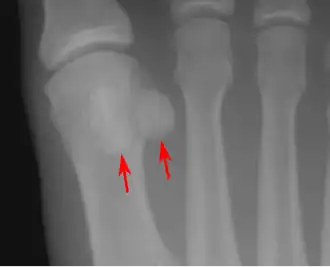

![]() Сесамовидные кости в области дистального отдела первой плюсневой кости | |

- стопа — две сесамовидные кости в области соединения первой плюсневой кости с первым пальцем (внутри сухожилия короткого сгибателя большого пальца стопы)[2].